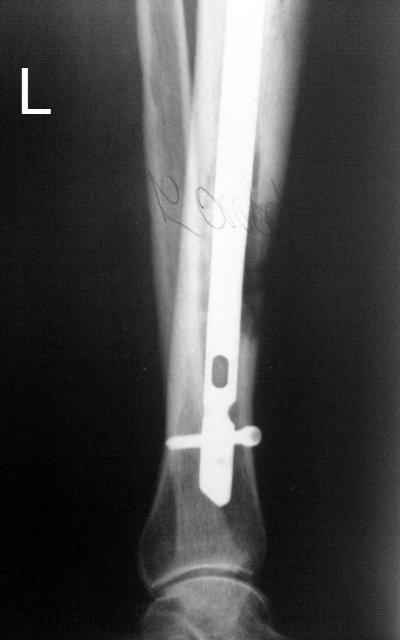

Итак, в настоящий момент больной пришел к нам с полной нагрузкой на оперированную конечность и с такой картиной (см. приложение). Участок мягких тканей с передней стенкой нижней трети ББК, выгнил и представляет дефект 2×2,5 см. На перевязке - циркулярный(?) некроз костной трубки.

Пациенту за 70 лет. Мои соображения: 1 этап - резекция tibia + косая остеотомия fibula + «острое» укорочение + IM цемент-гвоздь с а/б + beads. 2 этап (по заживлению раны) – удаление цемент-гвоздя + (LATN) Lengthening and Then Nailing. Прошу помощи по тактике.Никита Заднепровский

Сегментарного некроза не видно. Есть только краевой дефект спереди, задняя стенка вполне хорошая, и со стержнем есть условия для ее утолщения со временем. Так что проблему должна решить местная санация (если доступно, использовать VAC). Если грануляции не закроют все, что надо закрыть, придется делать пластику полнослойным лоскутом. Идеально бы - с микроососудистым анастомозом.

Тогда можно рассмотреть вопрос одновременного удаления штифта, мышечной (в данной области применим проксимально отсеченный лоскут камбаловидной мышцы) или микрохирургической (что более надежно) пластики дефекта мягких тканей, остеотомии проксимального фрагмента большеберцовой кости, остеосинтеза блокируемым штифтом с а/б покрытием, наложения простого аппарата Илизарова (можно из полуколец) для дистракции на штифте. При данном варианте пациент сохраняет возможность полной опоры на ногу, что очень важно для заживления у пожилого пациента) и отпадает необходимость в проведении дополнительный операций (при благоприятном развитии событий).

Выкладываю картинки похожей пациентки. Извините, что без окончательных снимков (сейчас их нет под рукой). Правда мы имели проблемы у данной больной после снятия аппарата, когда промежуточный фрагмент большеберцовой кости сместился на 1,5 см дистально и отошел от проксимальной части кости. До сих пор у пациентки на снимках определяется лишь тонкая полоска кости по задней поверхности за штифтом (образовалось что-то вроде маленького регенерата)в области стыковки промежуточного и проксимального фрагментов. Больная пока решила подождать. Не хочет оперироваться, так как ходит не хромая, работает.